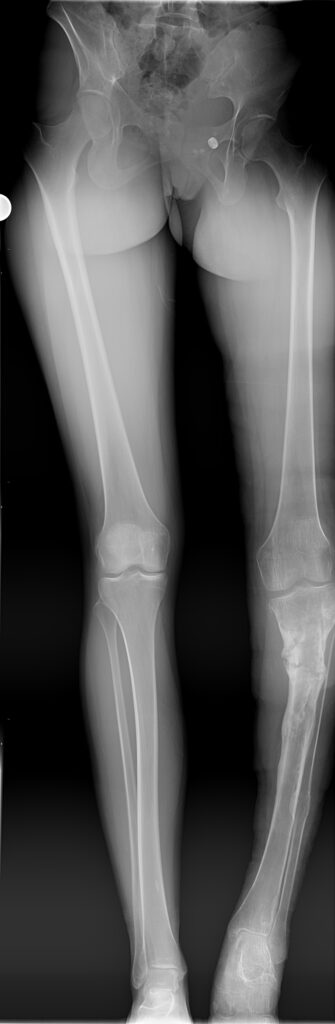

Ava (20×30)

Achondroplasia Dwarfism